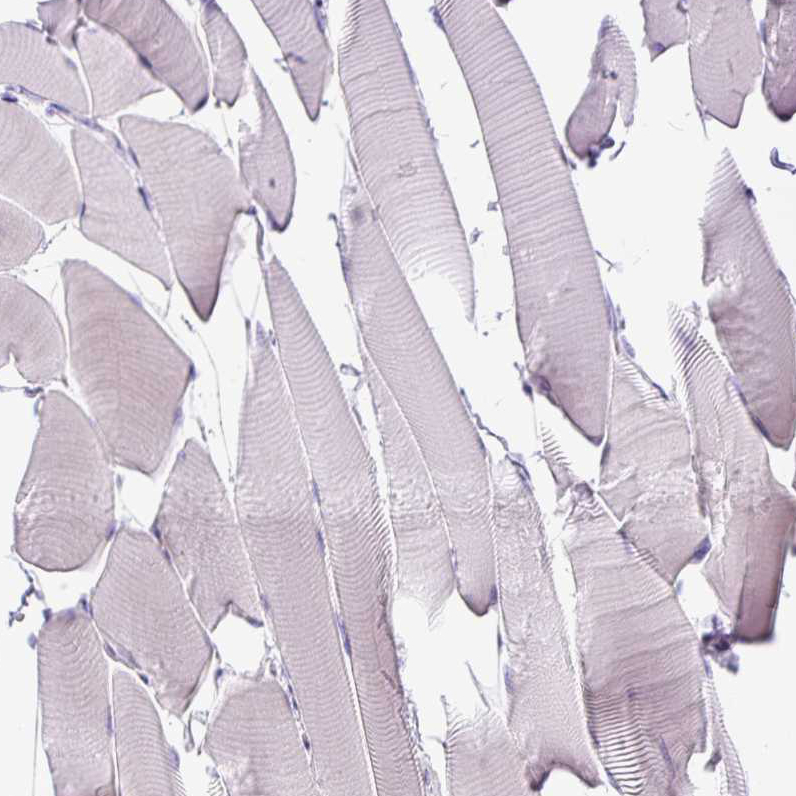

Immunohistochemical staining of human cerebral cortex shows weak cytoplasmic positivity in neurons.